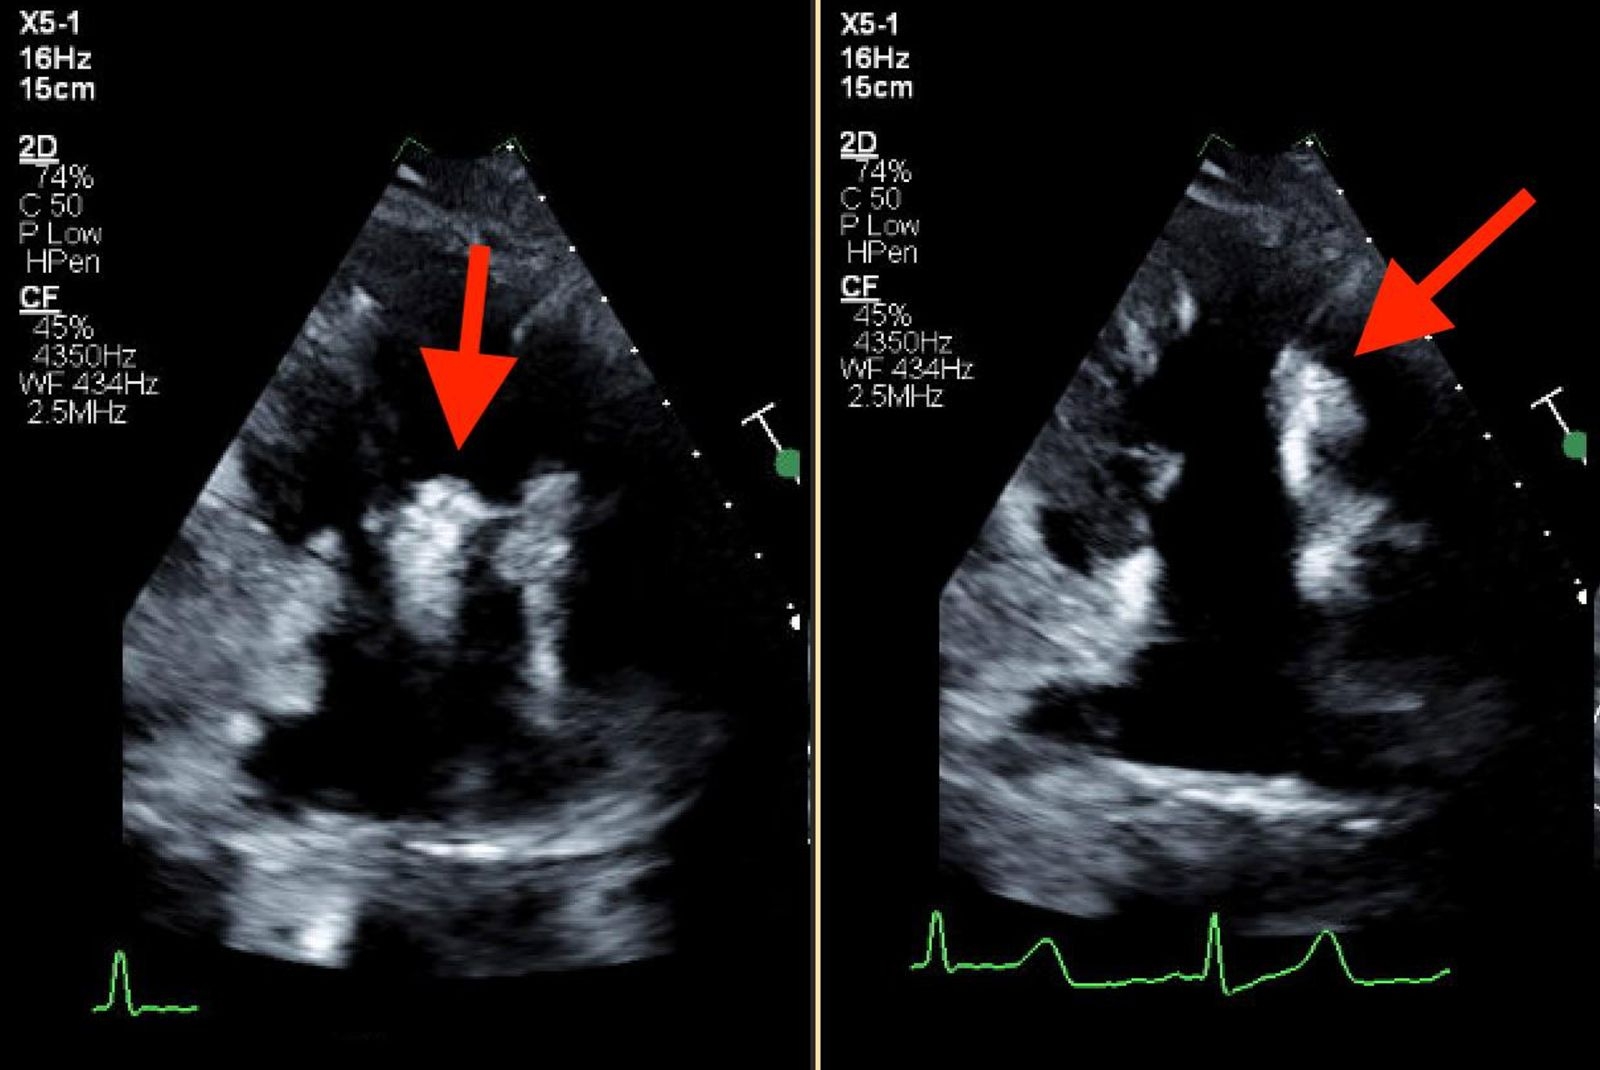

33-year-old female with a history of polysubstance IV drug abuse, hepatitis C infection, multiple hip surgeries with abscess drainage, tricuspid valve endocarditis with MRSA bacteremia, treated with IV Ceftaroline and daptomycin for 6 weeks via left PICC line, which was removed 2 weeks before her hospital presentation. The patient presented to the hospital with complaints of fever and generalized weakness, she was treated with broad-spectrum antibiotics, and investigations with TEE revealed mobile Tricuspid valve vegetation as well as a linear, highly mobile, tubular structure within the SVC extending into the right atrium, presenting a GFCS. CT chest also revealed multiple septic emboli, and blood cultures were positive for Serratia marcescens and ESBL Klebsiella pneumoniae. Patient was started on Anticoagulation with Eliquis and was evaluated by the Cardiothoracic surgery team for possible AngioVac, yet no good targets were found, and a decision was made to treat the patient medically without placing any further central lines. Unfortunately patient had signed out AMA after 1 week before completing her antibiotics course, yet she continued to take Eliquis outpatient. Patient returned to our Center 2 months later with similar complaints, TTE revealed large 3.8 * 2.35 cm highly mobile, irregularly shaped Tricuspid Valve mass that has significantly increased in size in comparison with prior imaging, and complete resolution of the previosly seen GFCS, Patient again left AMA refusing further treatments and investigations.

Ghost fibrin catheter sheath (GFCS) is a rare condition that can sometimes be a harmless incidental finding. However, it may also pose a risk of thrombosis and embolization, particularly in the context of infective endocarditis. While definitive treatment guidelines are lacking, antibiotics and anticoagulation are commonly used. AngioVac has been used in some instances, but its clear benefits has not been established. Our case demonstrated complete resolution of the GFCS with anticoagulation despite not being compliant with antibiotics.